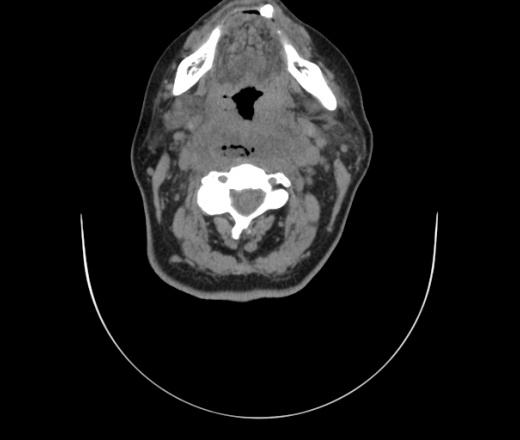

Женщина поступила в х/о спустя 4 дня после того как при употреблении карася подавилась костью.

Наличие газа в средостении на протяжении тел С2-С6 (медиастинальна эмфизема); рыбная кость на уровне тела С6.

При всем уважении, но говорить о медиастинальной эмфиземе, оценивая мягкие ткани шеи, как-то слишком резко. На мой взгляд, это ретрофарингеальное пространство.

Согласен с Вами; конечно, наличие газа в клетчатке ретрофарингеального пространства (затмение с опечаткой..). К сожалению, процесс "продвигается" к медиастиниту. Но почему никто, не отмечает наличие рыб. кости; или это для Всех очевидно?

Так вы уже отметили. Хотя ориентировал бы не скелетотопически, а на перстнечерпаловидный сустав.

Кость то мы сразу выявили, размеры где то 17*2мм, но ее так и не получается найти в этой каше